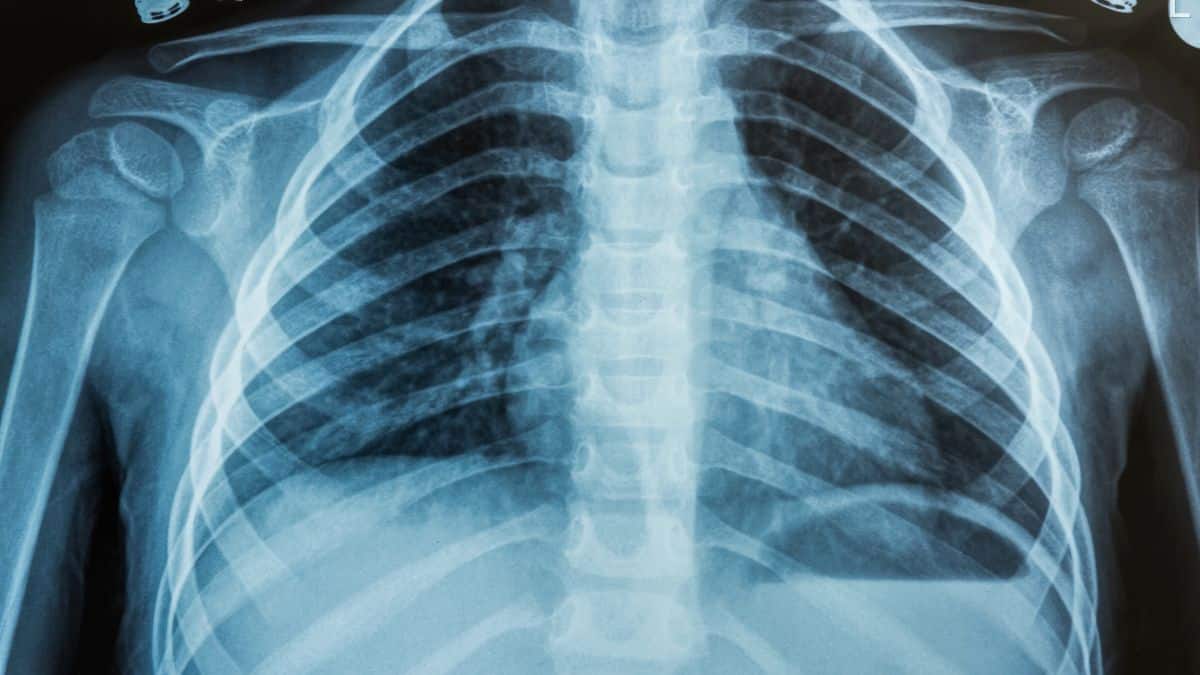

Une étude scientifique récente menée aux États-Unis apporte un nouvel éclairage sur le développement du cancer du poumon, l’une des maladies les plus mortelles à l’échelle mondiale. Cette recherche met en avant l’importance d’un processus métabolique souvent négligé, suggérant que notre régime alimentaire quotidien pourrait jouer un rôle significatif dans l’évolution de cette redoutable pathologie.

Les récentes découvertes mettent en lumière l’accumulation anormale de glycogène dans les tissus pulmonaires atteints par le cancer, en particulier dans les cas d’adénocarcinome pulmonaire (LUAD). Cette substance, habituellement impliquée dans le stockage d’énergie dans l’organisme, semble jouer un rôle crucial dans la progression rapide des cellules cancéreuses.